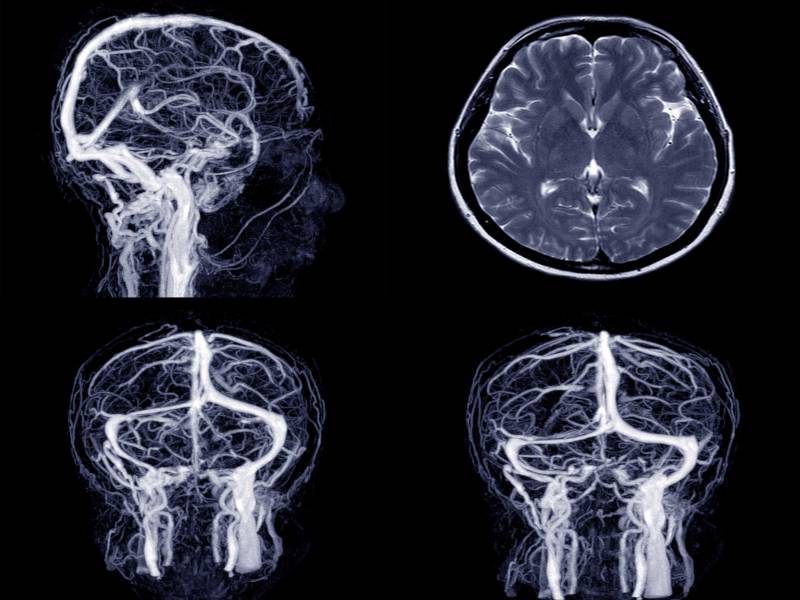

Neurocirurgia é a especialidade médica que se ocupa do tratamento de adultos e crianças portadores de doenças do sistema nervoso central e periférico, assim como tumores, doenças vasculares, traumas crânio-encefálicos e lesões raqui-medulares passíveis de abordagem cirúrgica.

O Serviço de Radiologia e Diagnóstico por Imagem próprio do Hospital do Rocio, localizado no Centro de Imagens, foi criado no ano de 2001 pa...